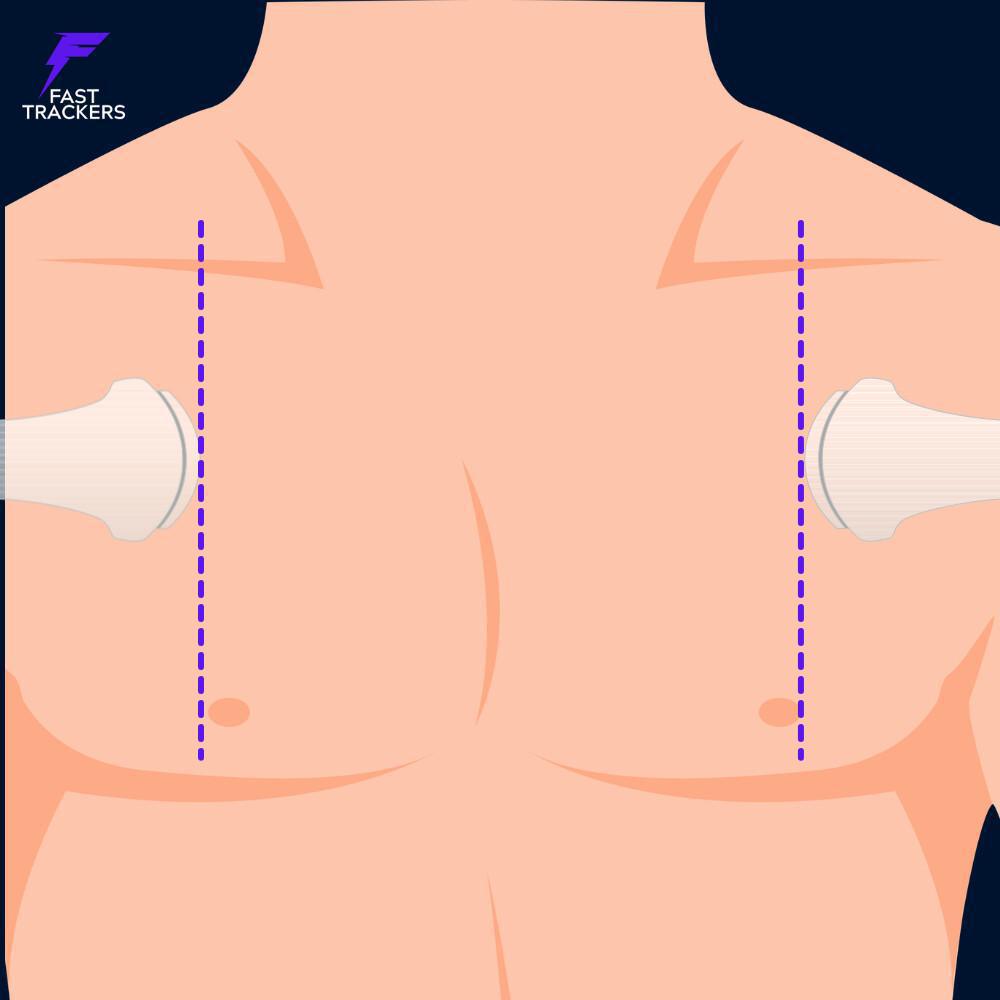

🔹 Recherche de pneumothorax

- Ligne médio-claviculaire

- 2e à 4e espace intercostal

- Coupe longitudinale intercostale

🎯 Repère clé : Deux côtes + ligne pleurale entre elles.